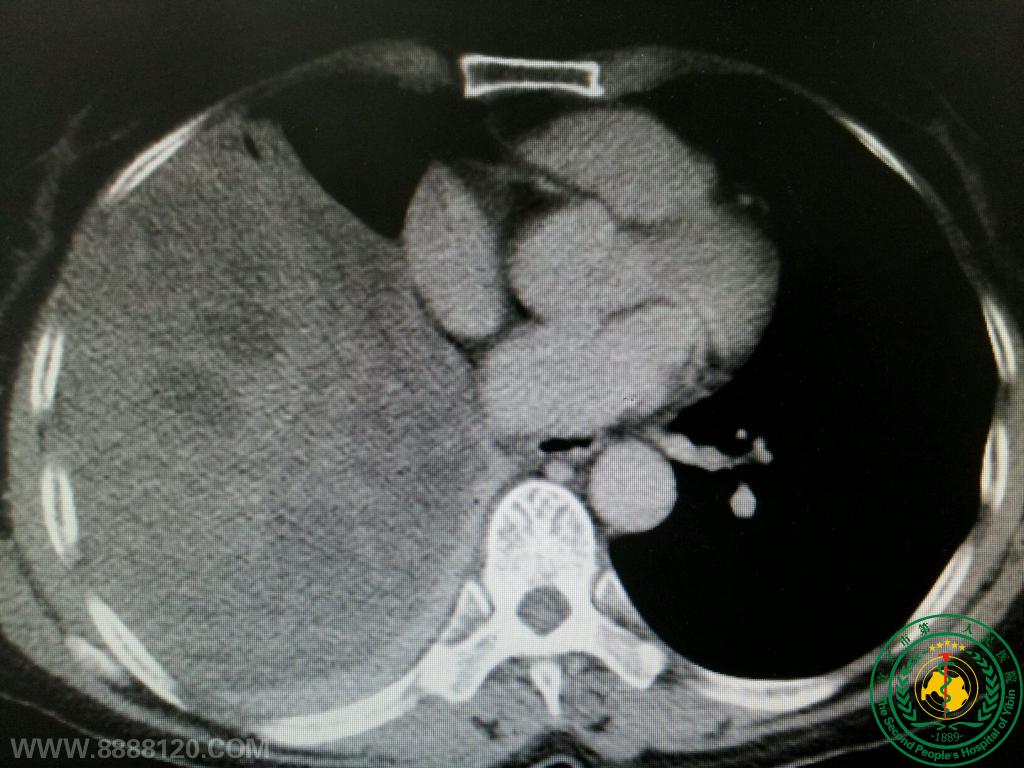

市二医院胸心外科手术成功切除一例巨大胸腔肿瘤报道

市二医院胸心外科手术成功切除一例巨大胸腔肿瘤报道4895